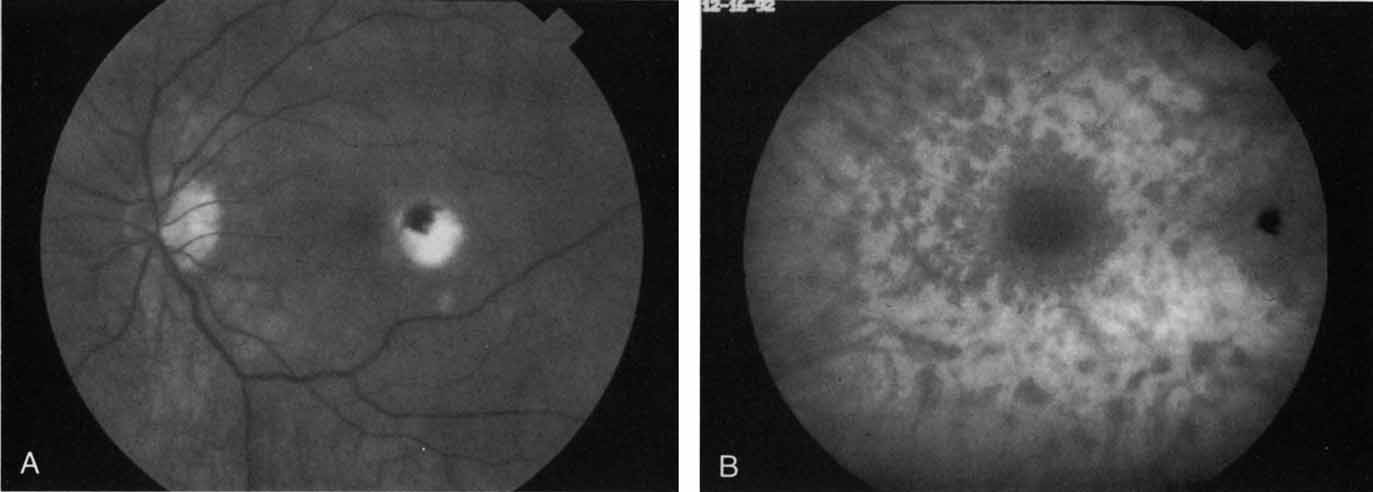

In contrast to multifocal choroiditis, ocular histoplasmosis syndrome does not demonstrate any large, hypofluorescent lesions on the ICG angiographic examination.69 Instead, there are frequently mid- and late-phase hyperfluorescent lesions in the posterior pole in areas that appear normal both clinically and on fluorescein angiography (Fig. 19). These hyperfluorescent lesions may represent sites of subclinical choroidal inflammation. The presence of these lesions on ICG angiography not only may serve to distinguish the histoplasmosis syndrome but also may serve to explain the apparent de novo appearance of new atrophic spots and CNV in what was previously presumed to be normal chorioretinal tissue.

Fig. 19 A. Clinical photograph of a patient with recurrent choroidal neovascularization associated with ocular histoplasmosis syndrome. A few focal “histo spots” are noted in the superior macula. B. Late-phase indocyanine green study demonstrating hyperfluorescence in the central macula corresponding to recurrent neovascularization. Multiple intensely hyperfluorescent dots are noted throughout the macular region, which do not correspond to any detectable lesion noted clinically or via fluorescein angiography. These focal spots may represent sites of subclinical inflammation at the level of the choroid.